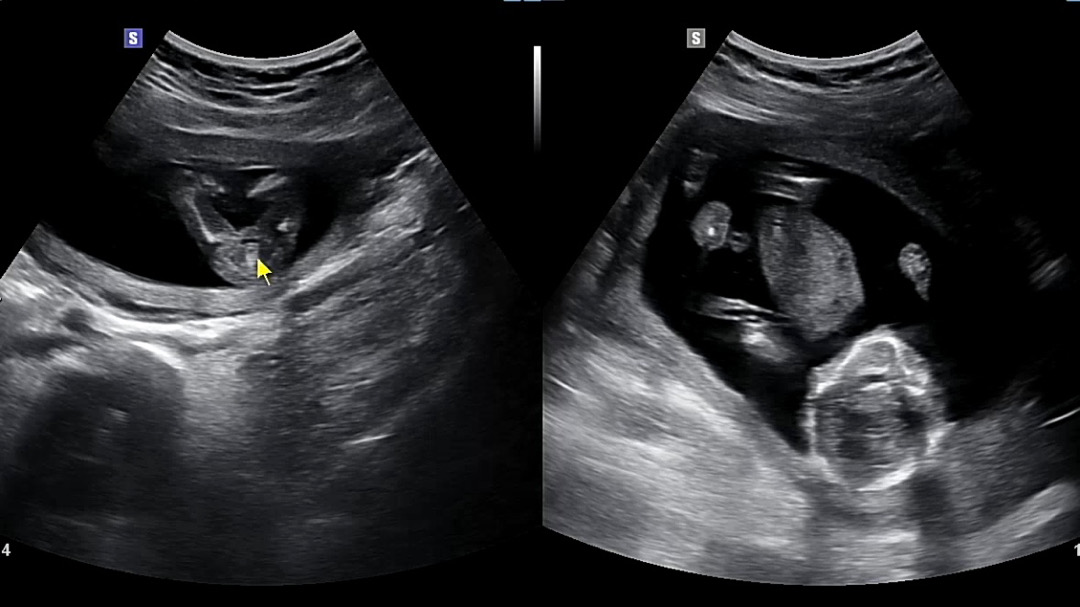

15주 3일 딸이래요 ~

원래 다음주 진룐데 오늘 궁금해서 초음파 보러 다녀왔다니 딸이라고 하네요! 음식 안가리고 다 잘 먹는 중이고 원래 마른 편인데 배도 펑퍼짐하게 ㅋㅋ 나오고 있어서 주변에거 다들 아들 같다고 했는데 반전이라 신기해요.